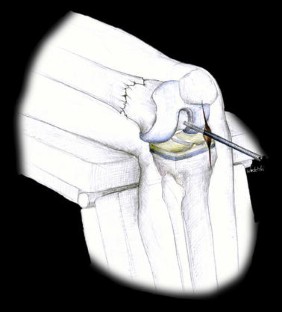

Abb. 3